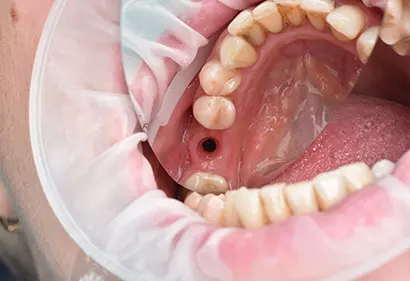

- Имплантация

- Лечение